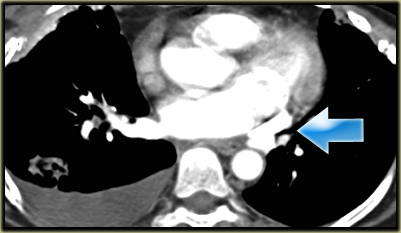

Left Superior Intercostal Vein.

This is an anastomosis between the accessory hemiazygos vein and the left brachiocephalic vein.

It courses along the lateral margin of the aortic arch (‘aortic nipple’).

It is a normal variant and if you look for this structure you will frequently notice it.

On the left a patient with a left superior intercostal vein.

Notice the ‘aortic nipple sign’.

On the left another example of a left superior intercostal vein.

It courses along the lateral margin of the aortic arch from the the accessory hemiazygos vein to the left brachiocephalic vein.